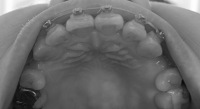

9月末の時点と全然違いがありませんが、一応今日の写真載せときます。